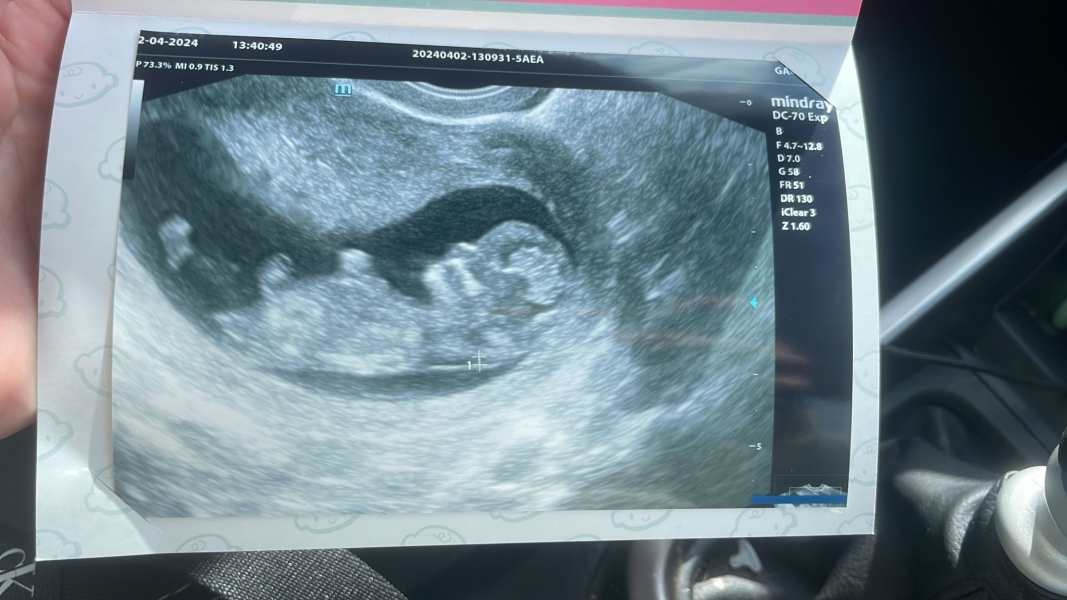

tink3rb3ll · 02/04/2024 17:16

Been for a scan today, now measuring 11+1.

Here's my scan pic, any guesses on the gender? I've always felt like I'm having a boy for some reason.

Booked myself in for a NIPT on Sunday.